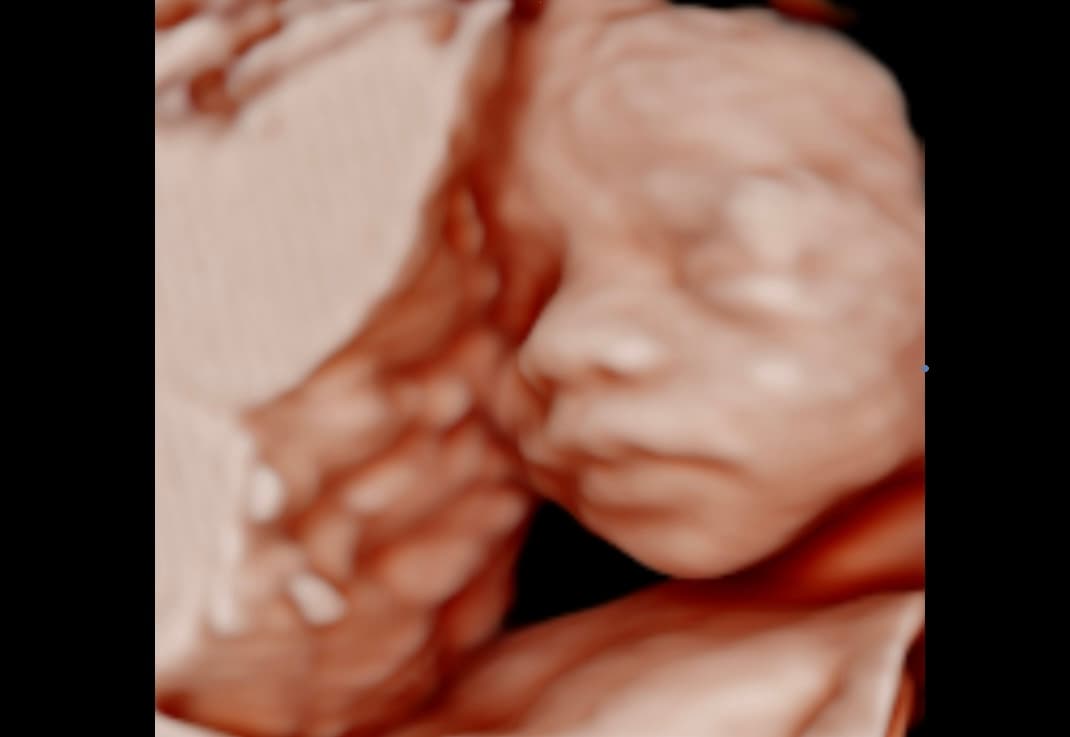

Explore our collection of ultrasound images and clinic photos. See the quality and clarity of our technology and the comfort of our facilities.

Book an appointment today and capture beautiful images of your baby. Our state-of-the-art technology provides clear, detailed ultrasound images for you to cherish forever.